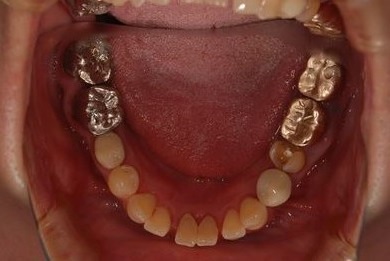

| 性別/年齢 | 女性 / 51歳 | ||||||||||||||||||||||||||||||||

| 主訴 | 前の歯の治療後の変色が気になる。詰め物がとれた箇所あり。痛みあり。 | ||||||||||||||||||||||||||||||||

| 治療方針 | セラミック治療にて、審美的回復を行う。 | ||||||||||||||||||||||||||||||||

| 治療内容 | オールセラミッククラウン7本(オールセラミック用土台1本)、ハイブリッドセラミッククラウン10本(ハイブリッドセラミック用土台9本)、ハイブリッドセラミックインレー1本 | ||||||||||||||||||||||||||||||||

| 総治療費 | 961,800円 | ||||||||||||||||||||||||||||||||

| 治療期間 | 10ヶ月 |